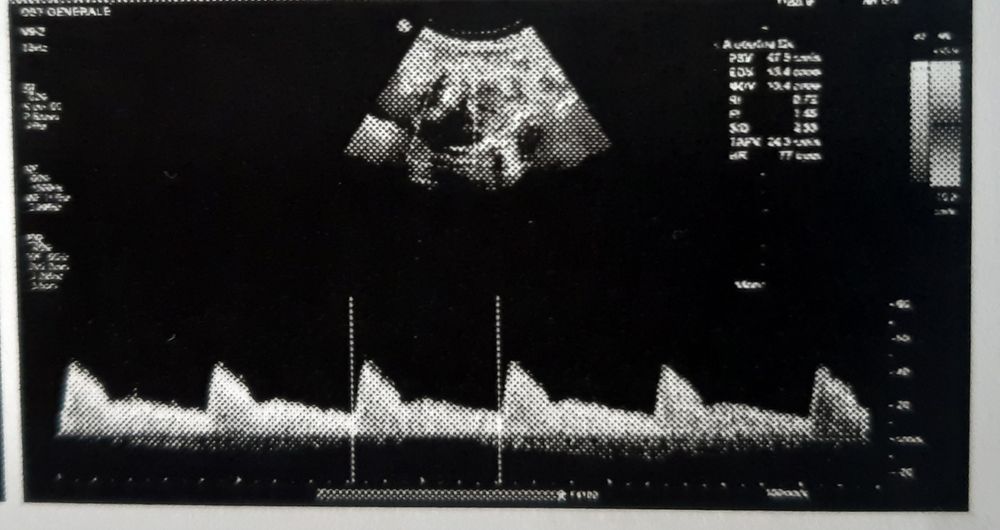

Не знаю, актуально ли, но увидела пост в дневнике и решила прочитать. ЧСС по английски - HR. Вижу на 1 фото HR 142 или 148, самая нижняя строчка. Остальные фото видимо артерии или что-то еще

Изображение Вот мое в 7 недель. Написано ясное, ровное. Так что не парьтесь , по картинке вы не посчитаете ЧСС

Галя Ромашова, Спасибо за фото! Я думала, что по фото можно: там нанесана шкала по 5 секунд, и думала надо считать пики, или как-то в этом роде. Просто везде пишут, что ЧСС - очень важный параметр на 1 скрининге, а у меня его опять нет. Буду надеяться что его утаили не потому, что плохо.

Все хорошо с сердцебиением , ровное. Видите повторяются фрагменты)) эт самое важное